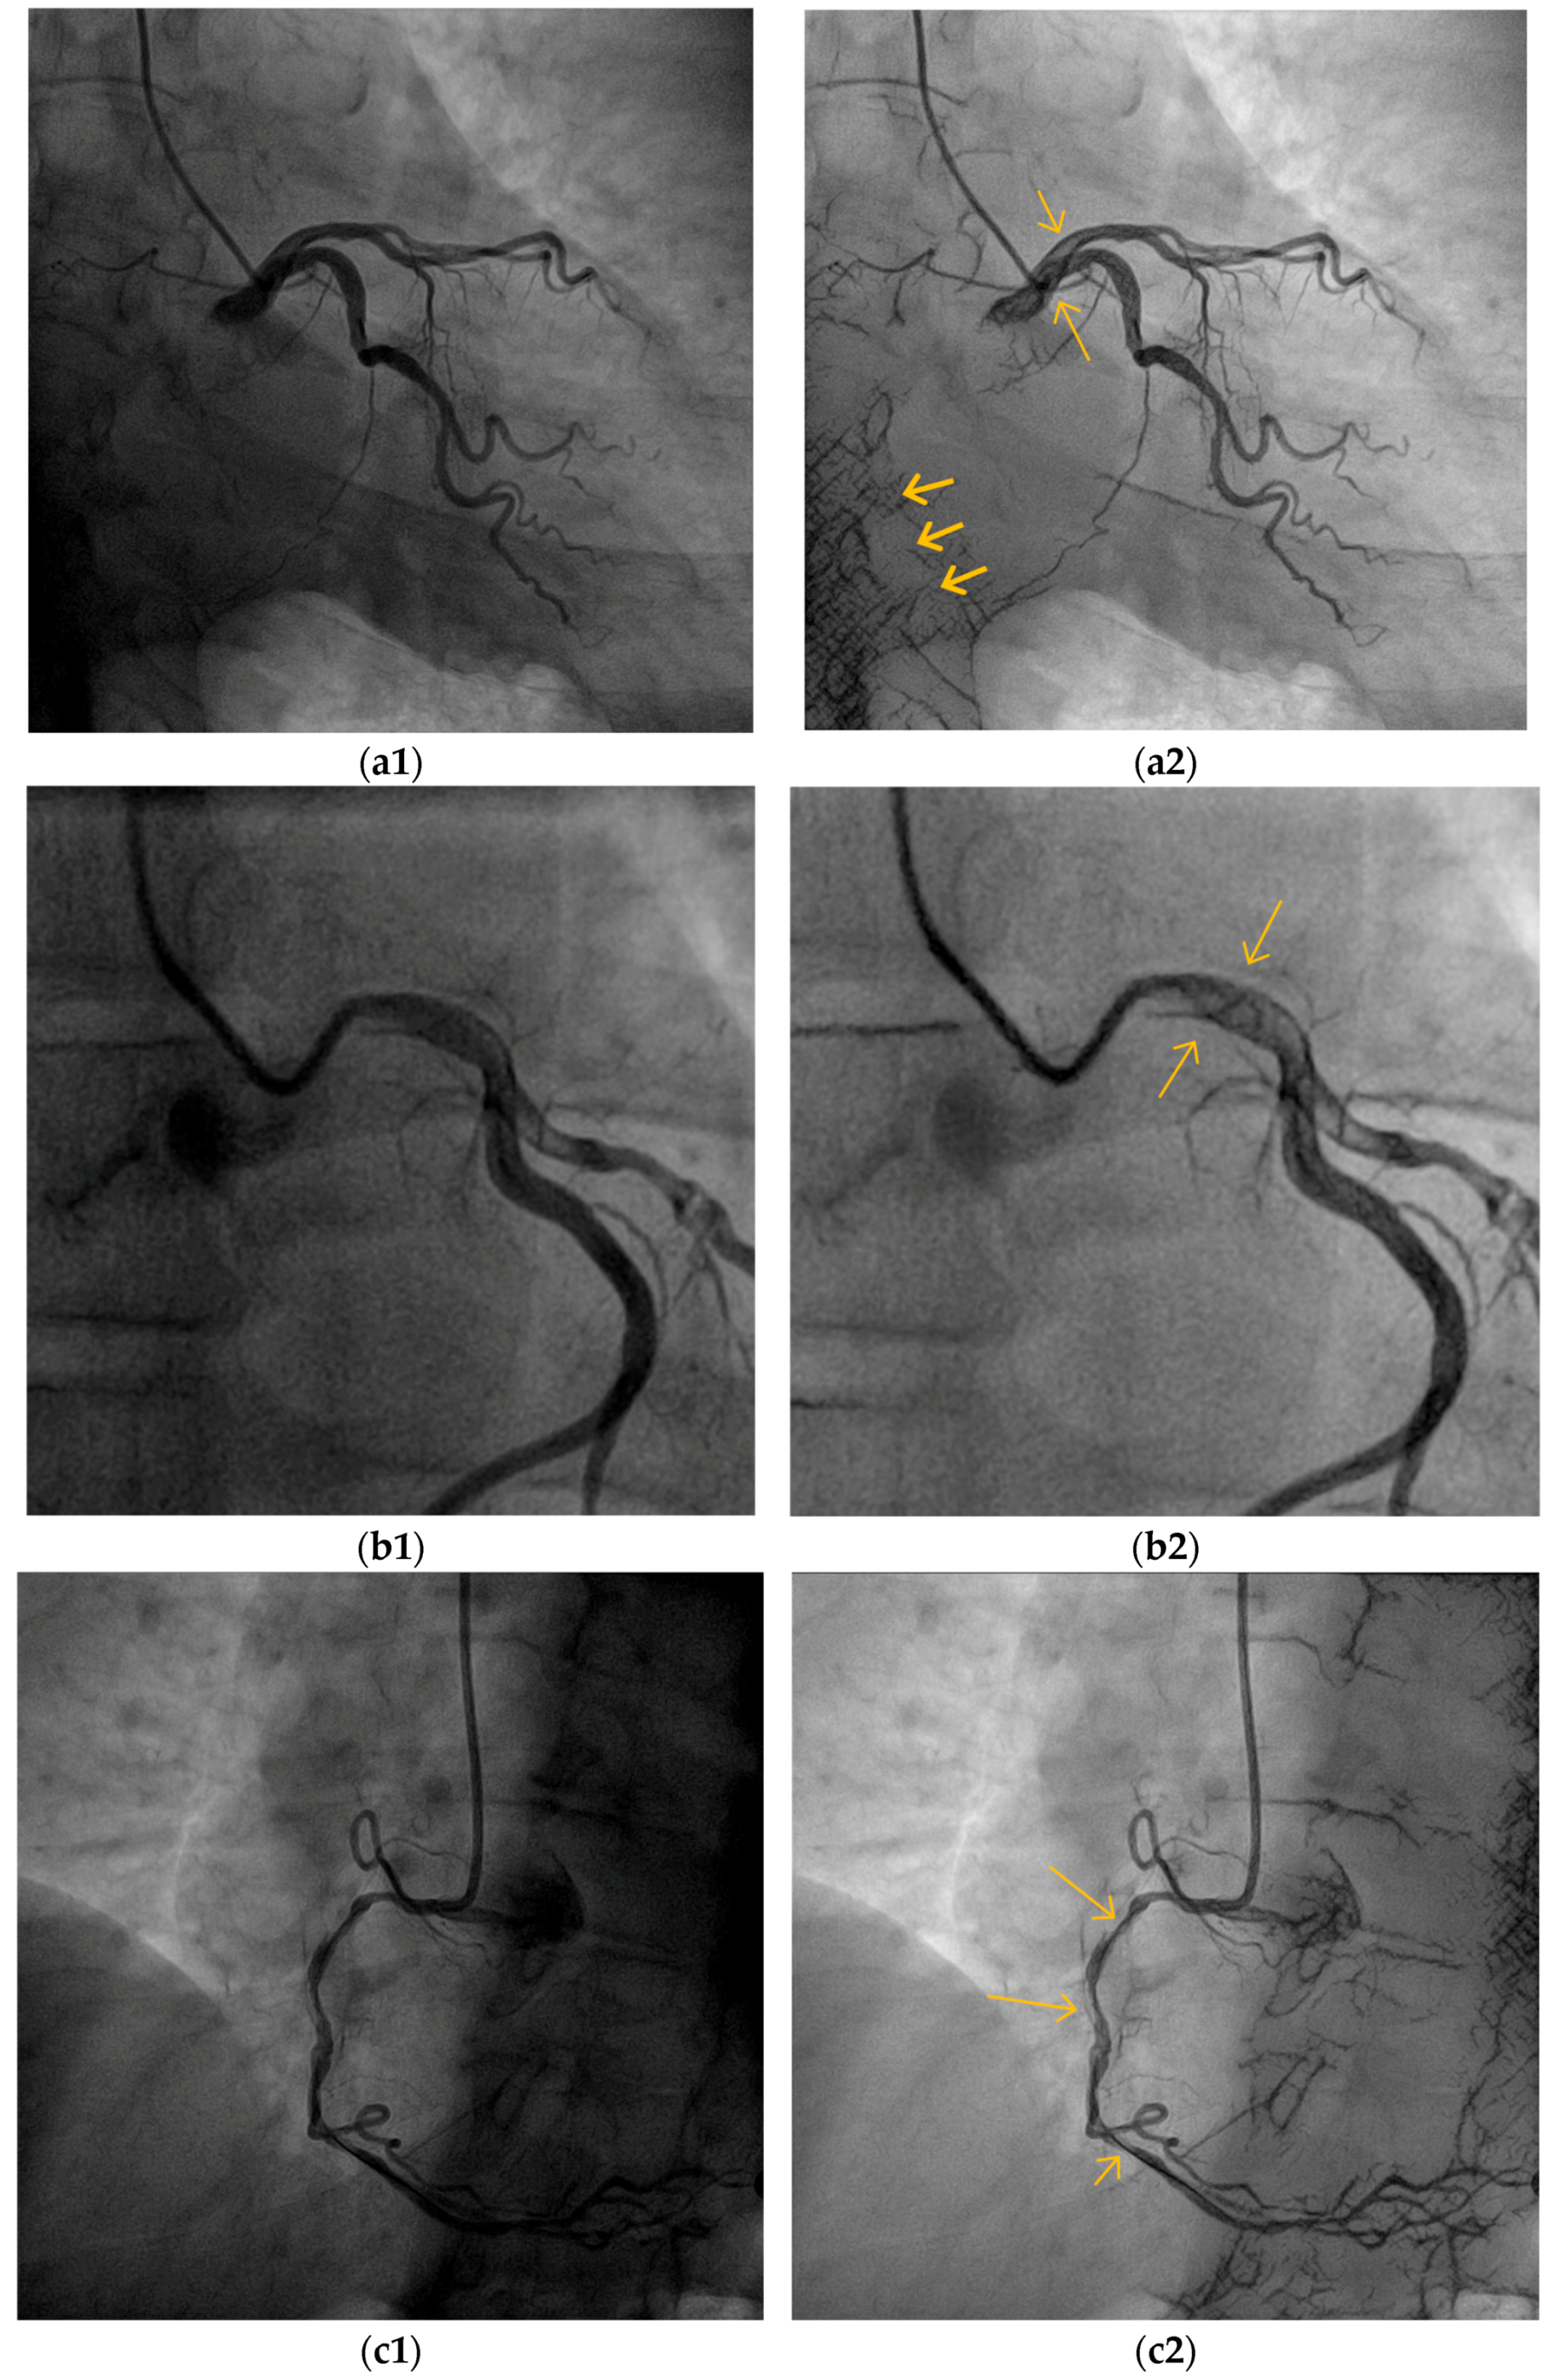

5.1. Overall Visibility Enhancement

5.2. Blood Vessel Interiors

5.3. Small Blood Vessels

5.4. Low-Contrast Agent, Low-Radiation, and No Contrast Agent